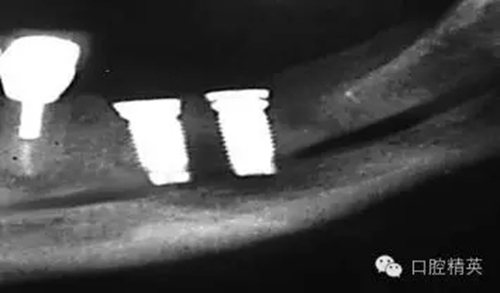

圖4:兩維曲面斷層影像難以獲得精確定位,有的醫(yī)生為了避免損傷下頜神經(jīng)管而應(yīng)用短種植體。這樣做的結(jié)果是增加了修復(fù)體-種植體長(zhǎng)度比,隨著時(shí)間的流逝會(huì)造成骨吸收,最終可能導(dǎo)致種植體折斷。骨內(nèi)折斷的種植體片斷需要手術(shù)取出,然后進(jìn)行植骨,骨質(zhì)愈合后再次種植,這些步驟不僅創(chuàng)傷大,而其從心理和經(jīng)濟(jì)上都會(huì)對(duì)患者造成損失。

如這個(gè)病例展示的,CBCT斷層掃描揭示了牙槽骨根方的凹陷。這樣就避免了術(shù)中的意外,醫(yī)生可以在術(shù)前完善的計(jì)劃,向患者交代清楚手術(shù)方法、風(fēng)險(xiǎn)、以及植骨所需增加的相應(yīng)費(fèi)用等問題。在兩維的放射影像中是無法預(yù)先觀察到這個(gè)問題的。僅使用兩維放射診斷帶來的另一個(gè)并發(fā)癥是種植體折斷。(圖4)前面提過,兩維曲面斷層影像難以獲得精確定位,有的醫(yī)生為了避免損傷下頜神經(jīng)管而應(yīng)用短種植體。這樣做的結(jié)果是增加了修復(fù)體-種植體長(zhǎng)度比,隨著時(shí)間的流逝會(huì)造成骨吸收,最終可能導(dǎo)致種植體折斷。

這種情況發(fā)生時(shí),骨內(nèi)折斷的種植體片斷需要手術(shù)取出,然后進(jìn)行植骨,骨質(zhì)愈合后再次種植,這些步驟不僅創(chuàng)傷大,而其從心理和經(jīng)濟(jì)上都會(huì)對(duì)患者造成損失。關(guān)于修復(fù)體—種植體高度比的問題也常導(dǎo)致修復(fù)醫(yī)生和外科醫(yī)生之間的爭(zhēng)執(zhí)。我們將在后面關(guān)于物理機(jī)械原因?qū)е碌姆N植體失敗模式的章節(jié)中進(jìn)一步討論關(guān)于修復(fù)“冠根”比的概念。